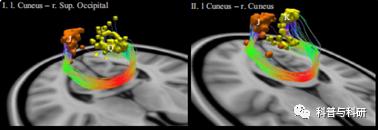

(2)基于ROI-ROI的确定性纤维追踪分析

1 弥散张量成像的配准

2 ROI的空间转换

3 用TrackVis进行纤维追踪

4 纤维束的量化统计与结果展示